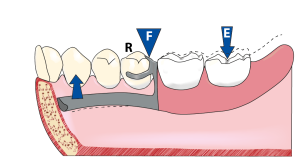

Another recommended approach involves a clasp design consisting of a mesial occlusal rest, a horizontal reciprocal arm, and a retentive arm placed in a distobuccal undercut. Positioning the occlusal rest mesially rather than distally, and locating the retentive arm within the distobuccal undercut, alters the direction of the stresses transmitted from the retentive arm to the abutment tooth. In a clasp design incorporating a mesial occlusal rest, the biomechanics follow the principles of a second-class lever. (Video 1-36).

Effect of second-class lever mechanics: The occlusal rest acts as the fulcrum (F) at one end of the lever, the distal extension base is subjected to occlusal force (E) at the opposite end,and the retentive tip of the clasp serves as the resistance (R) positioned between them.

When a mesial occlusal rest and a reverse Akers clasp, approaching the distobuccal undercut from the mesio-occlusal surface are used in distal extension dentures, as the denture base moves toward the tissue, the clasp tip moves into a deeper undercut area, and no torque is generated on the abutment tooth.